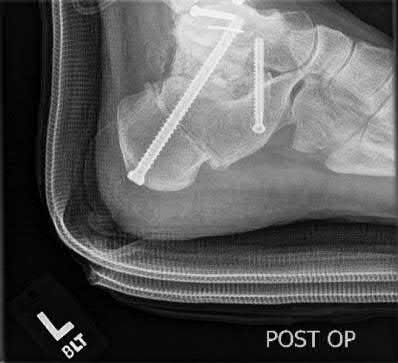

A 30-year-old male sustains a severe midfoot sprain. Radiographs reveal widening between the bases of the first and second metatarsals.

The primary ligamentous stabilizer disrupted in this classic Lisfranc injury connects which two osseous structures?

The Lisfranc ligament is the strongest ligament in the tarsometatarsal joint complex. It courses obliquely from the lateral aspect of the medial cuneiform to the medial base of the second metatarsal. It acts as the primary stabilizer of the second metatarsal base. Disruption results in the classic widening between the first and second rays, often with an avulsion fragment ('fleck sign').